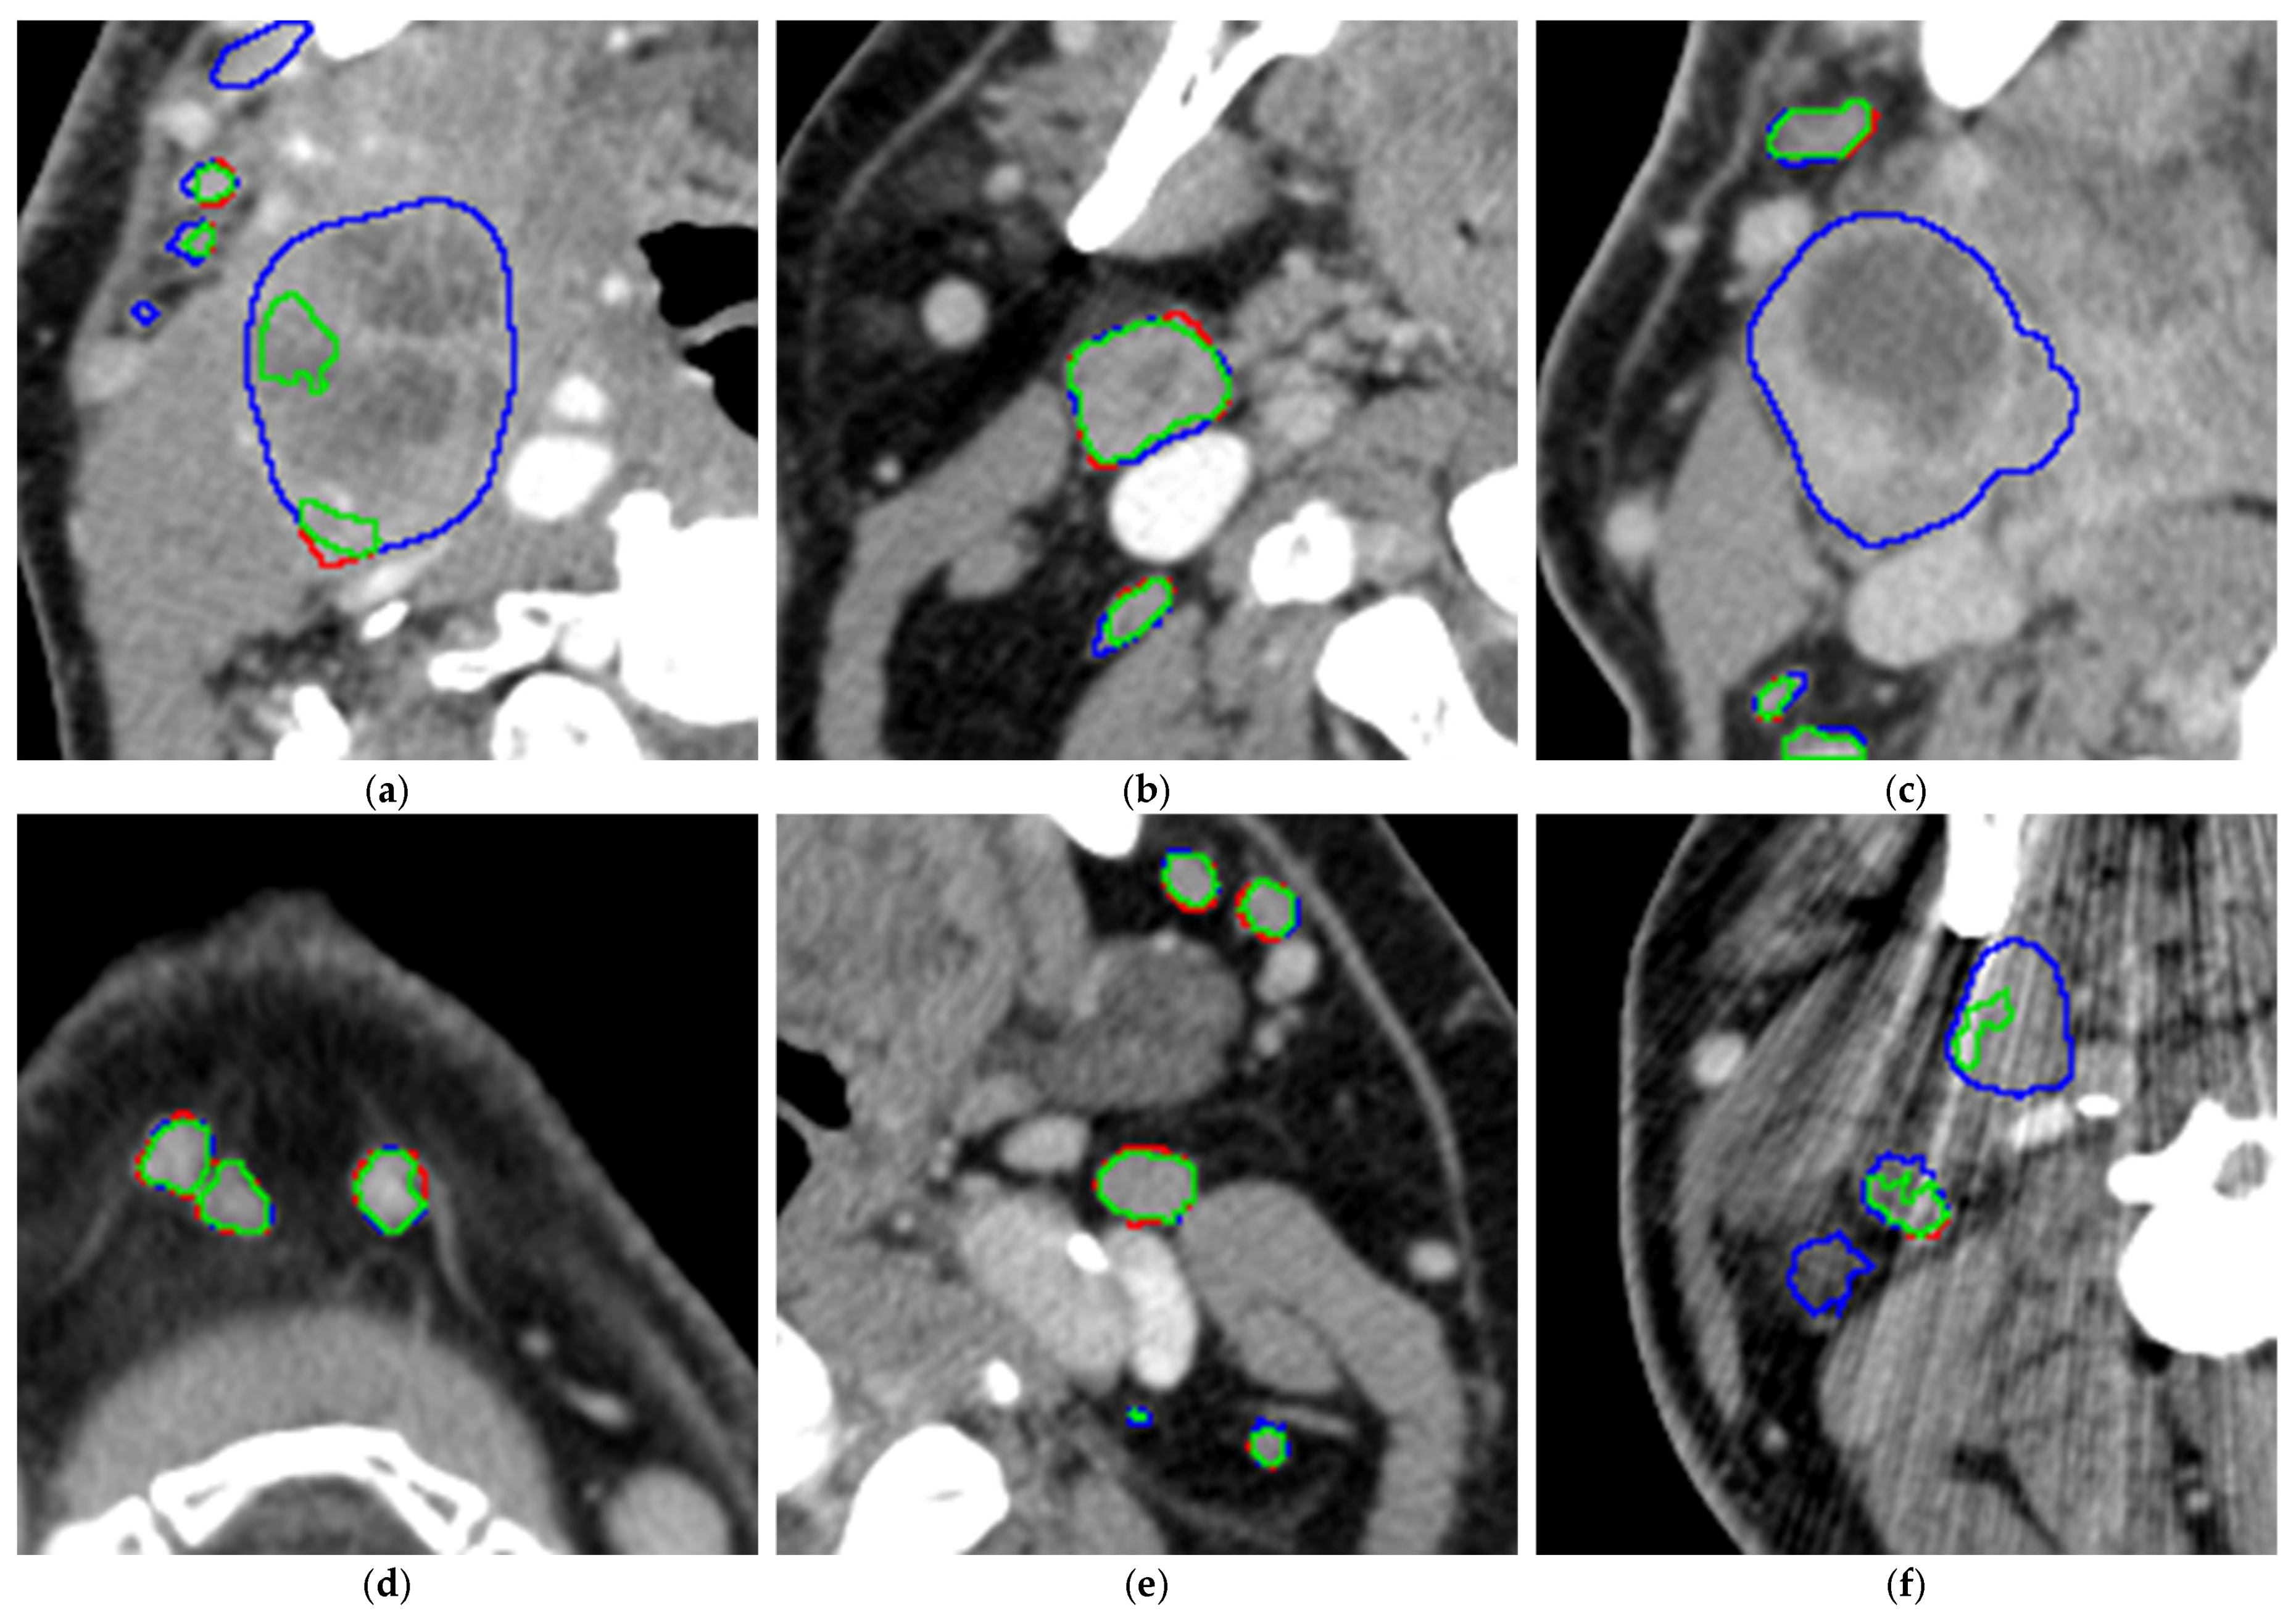

To obtain a better visual impression of the segmentation accuracy of both smaller and larger LNs, the radiologist looked at an overlay of the CT scan with both the manual segmentations and the segmentations performed by the AI model (see Figure 5).

Figure 5.

Relation between SAD and sensitivity for both normal (green dots) and metastatic (red crosses) lymph nodes. The blue line marks the threshold of 10 mm as an SAD for lymph nodes, which is the threshold for metastatic lymph nodes according to RECIST 1.1.

The model tends to leave out the necrotic parts of the metastatic LNs (please see Figure 6a,c), especially for large LNs, while for smaller LNs, it is often able to segment the necrotic center (see Figure 6b). For smaller LNs, the segmentations are accurate (see Figure 6d,e). In addition, metal artifacts from dental implants may affect segmentation accuracy (see Figure 6f) and thus recall.

Figure 6.

(a–f). Analysis of the segmentation overlays on 6 example CT slices (green: correct segmentations, blue: false-negative segmentations, thus manually segmented areas left out by the model, red: false-positive segmentations, thus areas segmented by the model but left out in the manual segmentations).